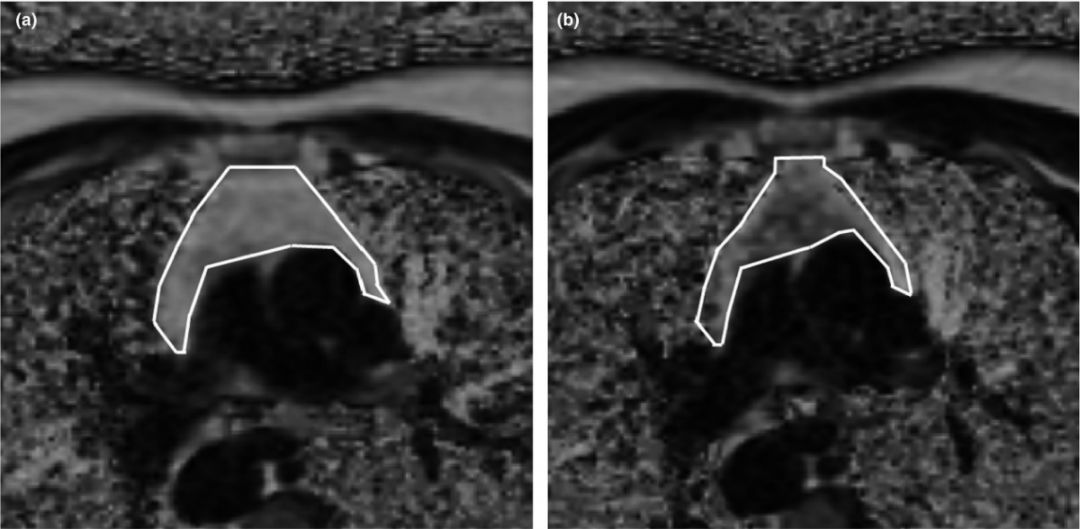

上图显示了一名自愿者在试验开始(左)和第9个月(右)时的MRI扫描结果。白色框线代表胸腺的边界,内部颜色变深表明胸腺内的脂肪减少。